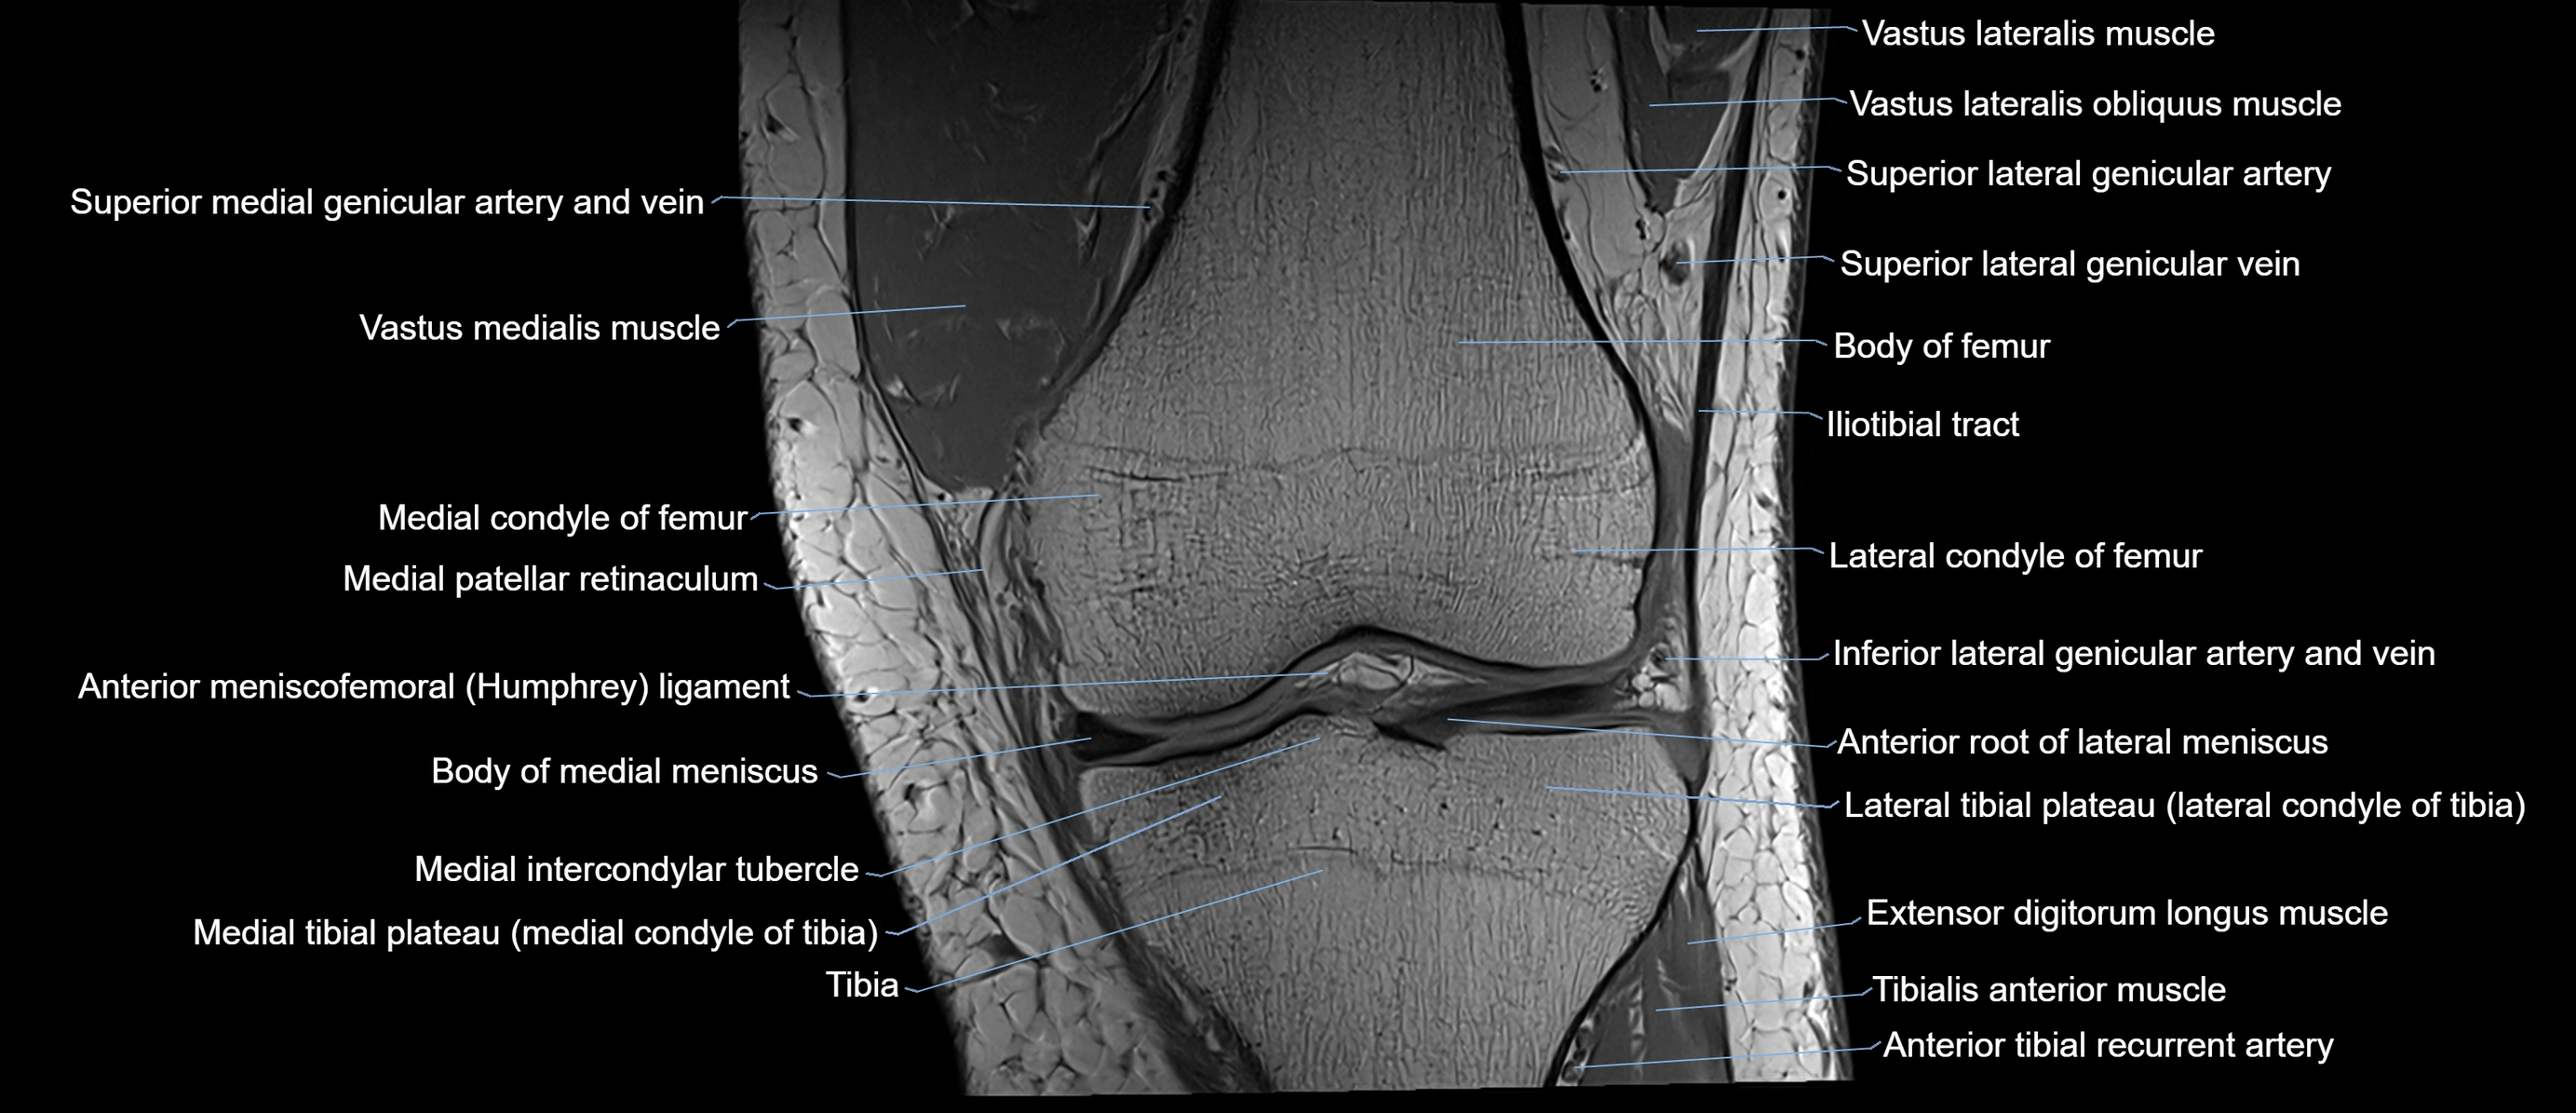

- Anterior root of lateral meniscus

- Body of medial meniscus

- Medial intercondylar tubercle

- Medial tibial plateau

- Extensor digitorum longus muscle

- Tibialis anterior muscle